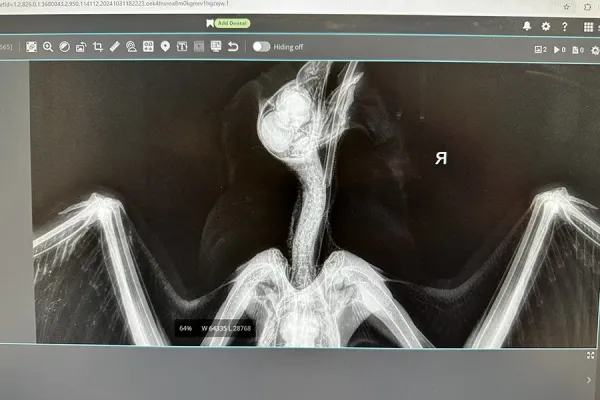

Since there were no discernable fractures, Dan packed up his little charge and drove off to meet Dr. Michael Taylor for x-rays and an expert assessment. X-rays confirmed that there are no fractures, but that the little fella suffered extensive nerve damage from overstretching of the left wing (brachial area). At this time, we have no idea what caused the trauma. The Doc also discovered some inflammation of the liver which could be entirely unrelated.